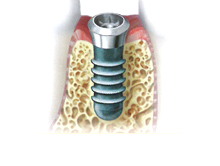

インプラントとは、歯が抜けてしまった部分へチタン製の人工歯根を埋め込み、その上に人工歯を取り付ける治療法です。

インプラントの構造

- インプラント治療は、チタンでできた人工歯根(インプラント体)を骨の中に埋め込み、その上に歯を再現する治療方法です。自然で違和感が少ないのがインプラント治療の特徴です。自然の歯と同じように食事がとれます。